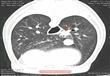

وأشارت الصحيفة إلى أن الأطباء عثروا على شوكة يبلغ طولها حوالي 8 سنتيمتر في قلب كلبة تدعى ميني.

ولفتت الصحيفة أن الأطباء عثروا على الشوكة، في الوقت المناسب، لأنها أثرت على رئتيها، وكادت أن تقتلها.